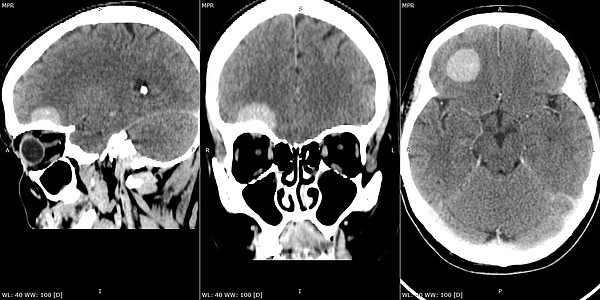

Малоинваз.